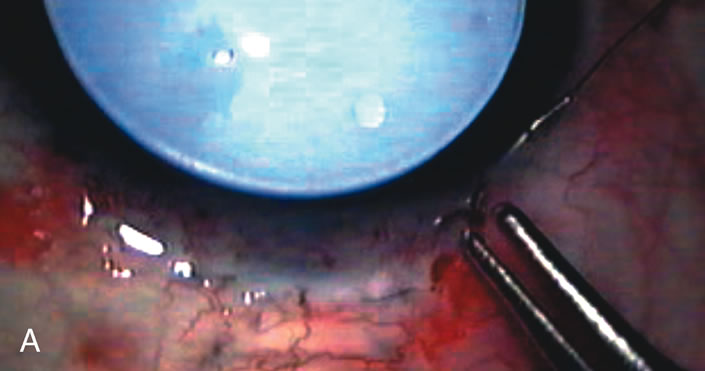

Fig. 1. The anatomic advantage of small incision cataract surgery for the glaucoma patient. A. Long-term bleb function with a large cataract incision is difficult to achieve with either ECCE-trabeculectomy or trabeculectomy followed later by ECCE. This bleb failed to form sufficiently when combined with large incision ECCE. The inflammation, bleeding, and long-term wound healing with stimulation of fibroblasts associated with this technique are more likely to cause bleb failure. In addition, the increased iris manipulation necessary to deliver the nucleus and subsequent iris repair adds to the long-term breakdown of the blood aqueous barrier. B and C. Two-site phacotrabeculectomy has the advantage of small incision cataract surgery combined with separate site trabeculectomy. The incision size is one third the size of the standard ECCE. The inflammation is less severe, and cataract wound healing is confined to the temporal area. Visual rehabilitation with phacoemulsification and foldable IOL is much faster. Phacoemulsification allows successful lens extraction even in the unfriendly environment of a smaller pupil compared with ECCE. The trabeculectomy is performed in an entirely different site, well away from the wound healing associated with temporal phacoemulsification. The likelihood of this filter functioning long-term is greater than with ECCE-trabeculectomy. D. The surgeon also has the option of single-site phacotrabeculectomy with foldable IOL. Both the lens extraction and trabeculectomy are performed through one small 3.5-mm limbal incision.

Fig. 2. Wound modulation and revision. A. MMC decreases the likelihood of bleb failure in high-risk eyes undergoing combined cataract and glaucoma surgery. Overusage of this potent cytotoxic drug should be avoided owing to a myriad of problems related to the formation of an avascular bleb. B. Office-based laser revision of the operative wound allows for increased postoperative flexibility with less complications. The correct number and tension of scleral flap sutures allows the surgeon to strive for a safe immediate postoperative IOP range. When fibrosis occurs at approximately 1 week, suturelysis or release of sutures increases filtration while avoiding unwanted hypotony.

In years past, patients with both cataract and glaucoma frequently provided overwhelming surgical challenges for the ophthalmologist. The ability to carry out phacoemulsification through a 3.2-mm corneal incision along with inserting a foldable IOL is a vast improvement over 11-mm incisions that were common a decade ago (Fig. 1). The anatomical and inflammatory changes to the eye are less with small incision techniques, improving the likelihood of success with concomitant glaucoma surgery. Pharmacologic inhibition of fibrosis along with postoperative wound revision increases the long-term success rate of filtration surgery when combined with lens extraction. (Fig. 2). The learning curve may be steep at times, but the blending of cataract and glaucoma surgical skills slowly falls into place as the surgeon constantly learns and upgrades his or her technique.